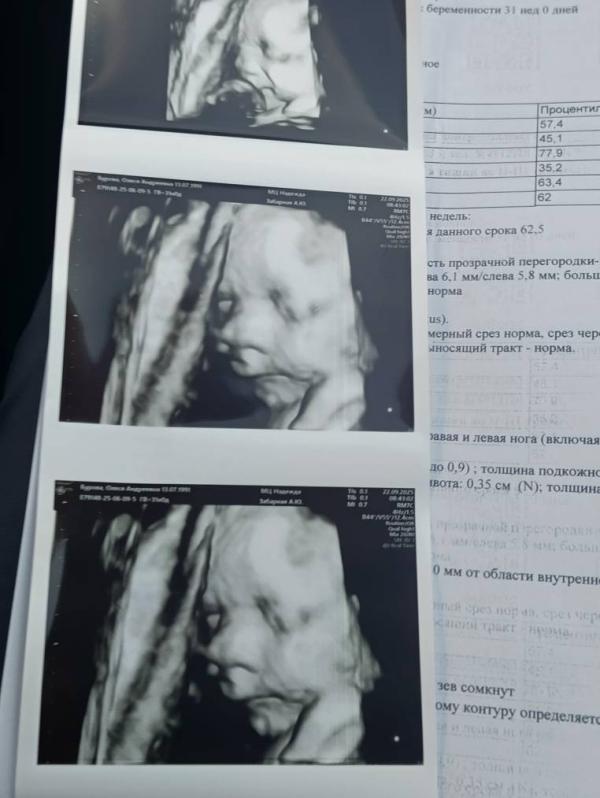

Доброе утро всем!Сходили на встречу с нашим малышом.У нас всё хорошо 🙏🥰Весим 1820кг💪 соответствуем сроку❤️

На 1м снимке будто кулачок, как мило 🥹